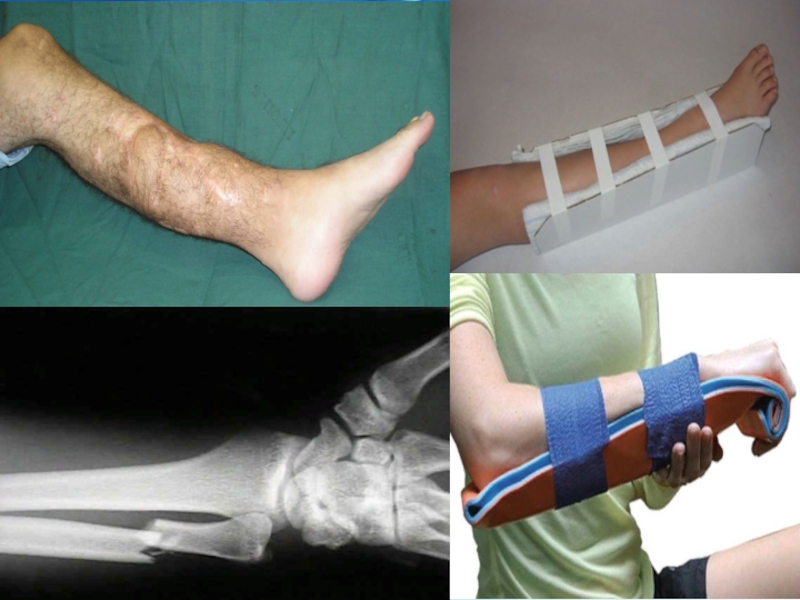

Слайд 11Переломы

Переломы — это повреждения целостности костей. Они могут произойти из-за механического

воздействия тупого предмета или падения человека на твёрдую поверхность. Переломы бывают закрытыми и открытыми. Отличие между ними в том, что в одном случае костные отломки выходят наружу через повреждённую кожу (открытый перелом), а в другом они находятся внутри мягких тканей (закрытый перелом). Нередко отломки повреждённой кости смещаются относительно друг друга. Встречаются также переломы-трещины, при которых целостность кости не нарушена. Переломы чаще встречаются у детей и подростков.

Слайд 12Признаки перелома кости

Пострадавший испытывает сильную боль при малейшей попытке движения повреждённой

рукой или ногой. Он щадит повреждённую конечность, поддерживая её здоровой рукой, или принимает вынужденное положение туловища. Наблюдаются также деформация и некоторое укорочение повреждённой конечности. Может наблюдаться подвижность костей в необычном месте.

Слайд 13Оказание первой помощи при переломах костей

При закрытых переломах необходимо:

обеспечить покой повреждённой

конечности. Для этого наложить специальные шины. Если под рукой их нет, шину следует изготовить. В качестве материала можно использовать любой (желательно плоский) подходящий предмет: дощечку, фанеру, толстый картон, зонтик, палку;

срочно дать пострадавшему обезболивающее (анальгин или другое лекарство);

затем надо обязательно обратиться к врачу.